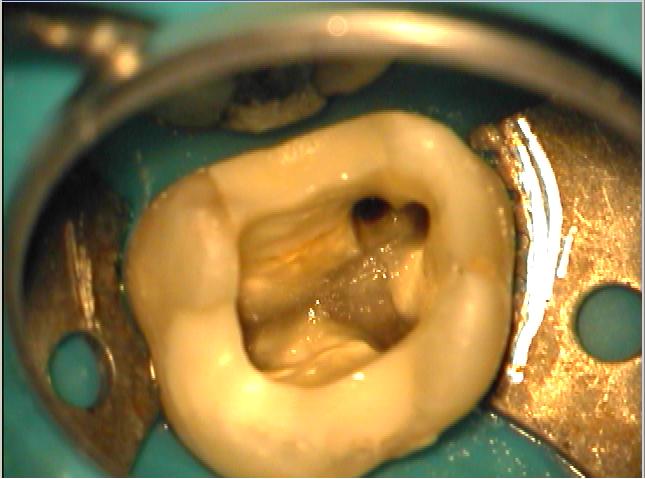

Klinische Situation nach Wurzelfüllung

Klinische Situation nach Wurzelfüllung. Die WF wird gezielt unter Mikroskopkontrolle 2-3 mm unterhalb der Orificien abgetrennt

Adhäsiver Verschluss

Adhäsiver Verschluss der Zugangskavität mit Verankerung im oberen Wurzeldrittel. Ein Stiftaufbau ist nicht mehr erforderlich